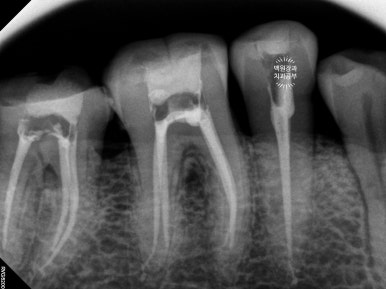

신경치료를 받은 어금니들에게 임시치아를 제작해주었습니다.

아래 앞니 부위는 임플란트 1차 수술을 시행하였습니다.

신경치료를 받고나면, 치아 가운데에 구멍이 생겨 치아가 구조적으로 약해집니다.

이를 보강하기 위해 임시치아를 제작해 드렸었어요.

그러면서 기다리는 동안 잘 아물은 아래 앞니쪽에 임플란트를 심어드렸습니다.

치료가 잘 되어있는 것이 보이고, 슬슬 윤곽이 잡혀가네요!!

약 3개월 정도 시간이 흘러 위 임플란트의 2차 수술을 시행하였습니다.

위턱뼈에 임플란트를 심은 경우 그 치유기간을 약 3개월 정도로 설정합니다.

건강한 뼈와 새로 위치된 임플란트 사이에 새로운 잇몸뼈 (신생골)가 골유착을 형성하는데 걸리는 시간이지요.

보시면 위 임플란트, 아래 임플란트 모두 뚜껑이 생겨있어요!